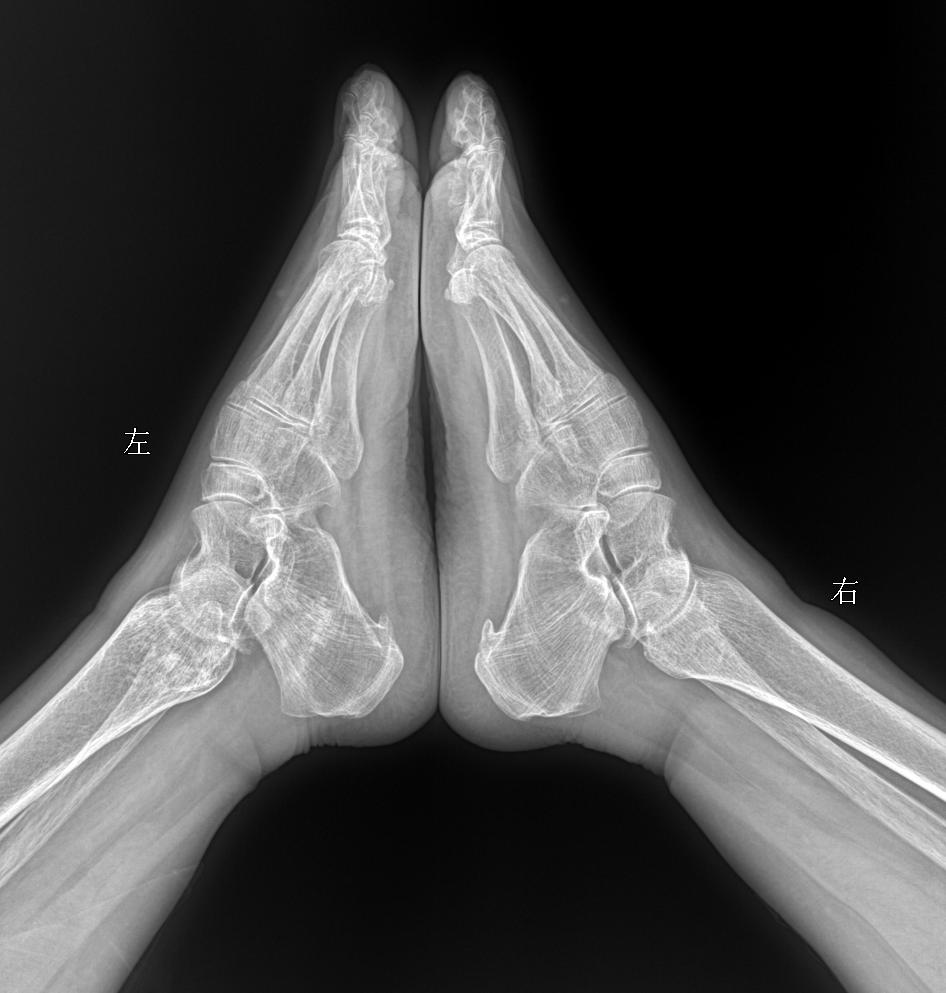

行走膝盖 脚底疼痛就诊 女69岁 考虑什么问题?